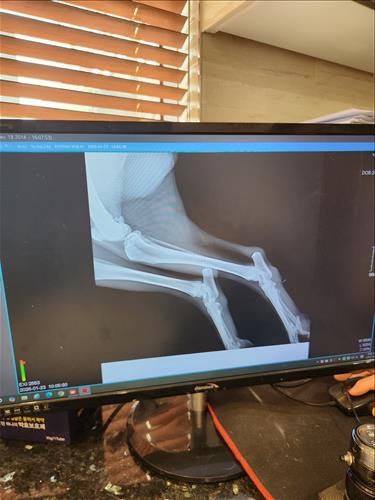

한달전에 자전거 산책이후 몇일후에 다리가 불편해 보여서 병원가서 소염진통제 처방받아서 먹이고 난뒤 몇일뒤 다리를 들기시작해서 병원가서 엑스레이도 찍었습니다. 지금 총기간이 한달정도 되었구요 미국 아키다 입니다. 체중은 40키로 정도이고요. 나이는 8.5살 정도 되는 수컷입니다. 왼쪽 다리입니다.

엑스레이 찍은 수의사님 말씀으론 뼈에는 아무 문제가 없다고 하네요.. 십자인대도 아무 문제 없다고 하시고.. 신경쪽 문제일수도 있다고 하시는대... 혹시나 다른병원을 가봐야 하는건지 너무 답답한 마음에 오늘 병원에 연락하여 엑스레이 사진 받아 왔습니다. 한번 봐주실수 있을까요. 부종같은건 없었는데 갑자기3일전부터 발바닥 조금위쪽 관절이 부종이 있는거같아요.. 만지면 불편해합니다. 갑자기 1달가까이 부종이없다가 부종이 생길수도 있나요??